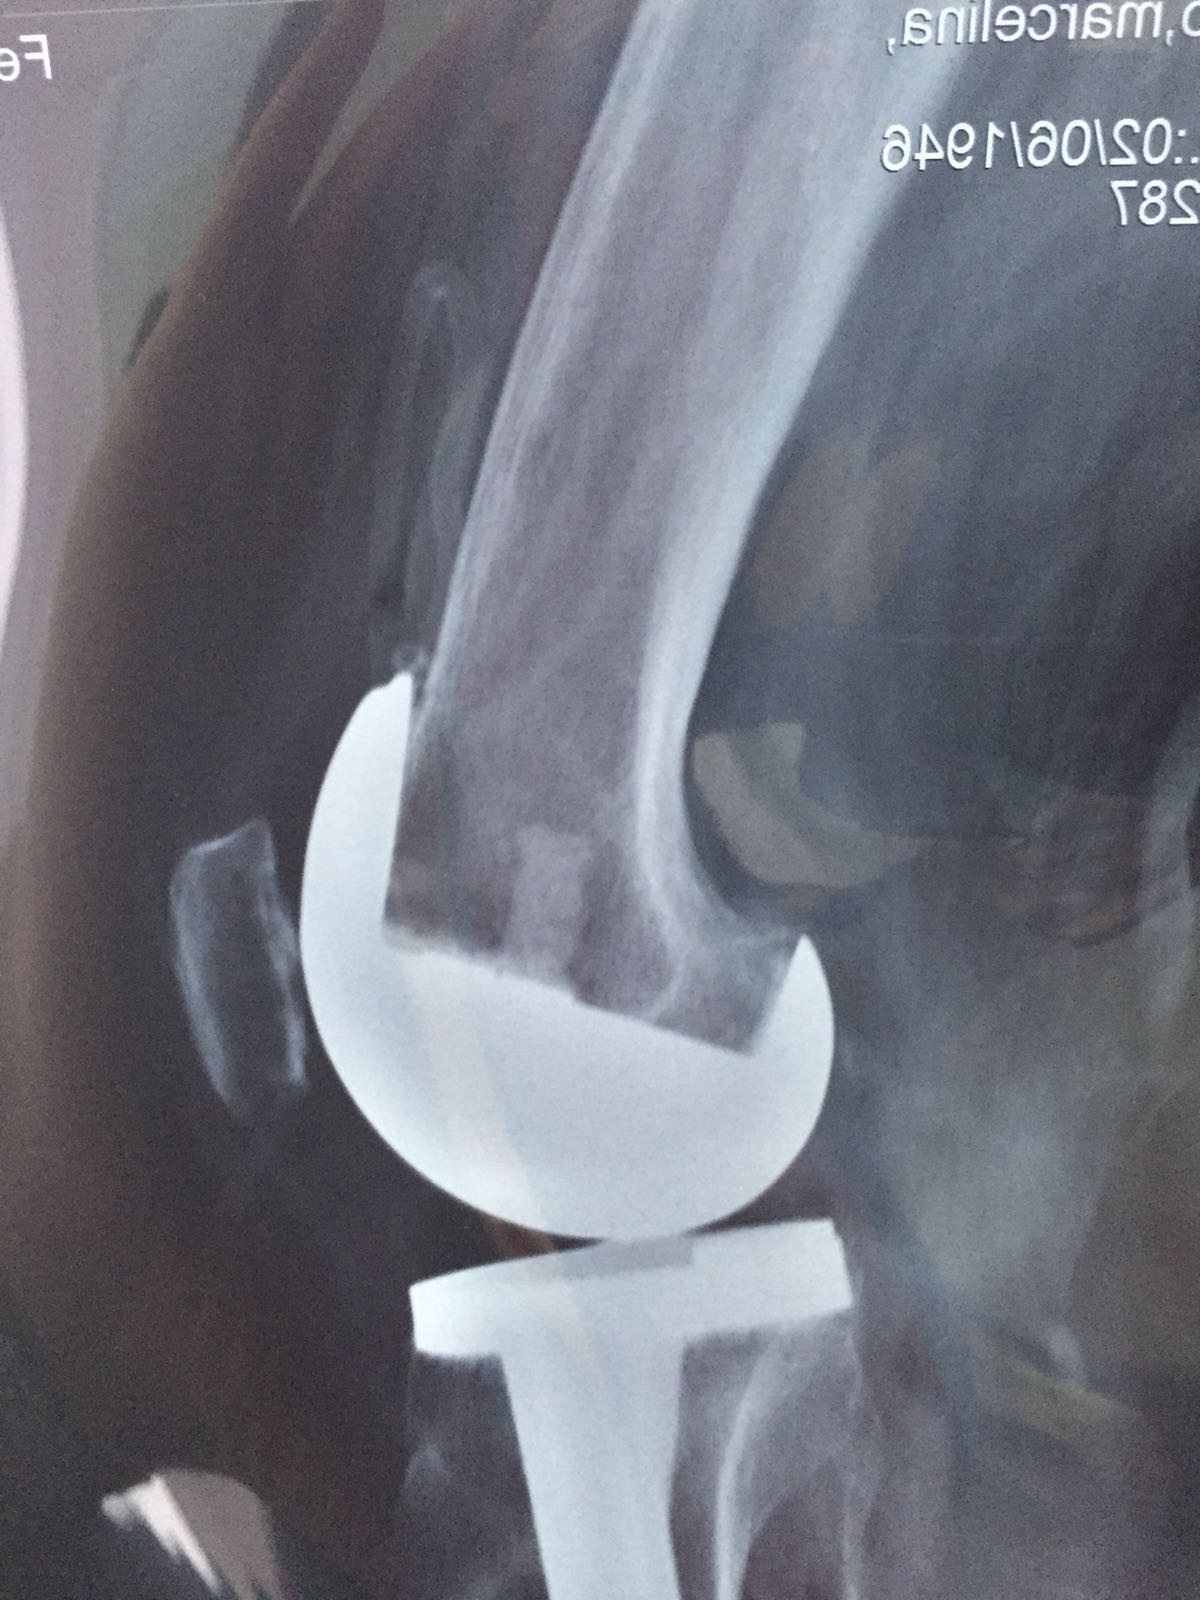

Prótesis de rodilla

El desgaste de la rodilla se llama Gonartrosis.

Artoplastía: Reemplazar parte de la rodilla dañada.